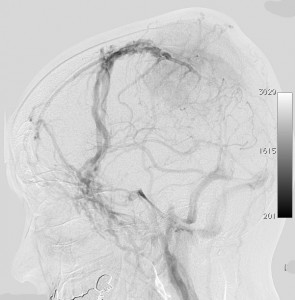

静脈洞交会髄膜腫 meningioma of the confluence of sinuses

若い女性に偶然発見されたものです。直静脈洞と静脈洞交会の接合部あたりに発生したもので,静脈洞はほぼ閉塞に近い所見でした。しかし,この部分の静脈洞は,テント硬静脈側副路が発達することがあるので,硬膜を含めた積極的な摘出をすることは絶対にできません。もしほんの少しでも流れがある直静脈洞を閉塞させると短時間に脳死になるような脳静脈圧亢進が生じる可能性があるからです。静脈洞内に少し取り残して(右下の矢印)手術を終了しました。手術後には定位放射線治療を行って再増大を防ぎます,